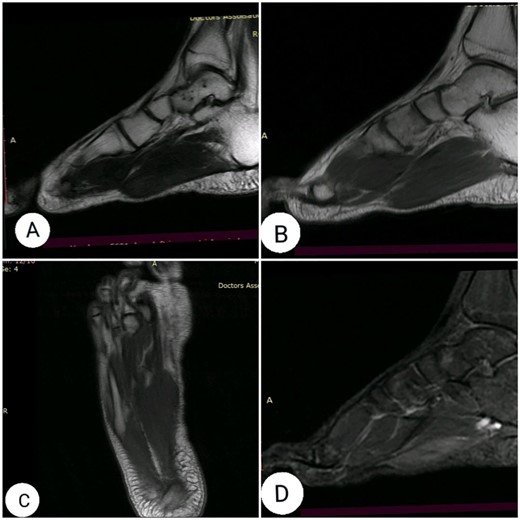

The clinical examination revealed flexion contracture of the third digit of the right foot with dislocation of the proximal interphalangeal (PIP) joint, limited passive and active extension of the second and fourth digits and the presence of little thickness in the skin over the dorsal aspect of the first metatarsophalangeal joint of the foot (Fig. 1). By palpation, there is a non-tender pseudotumor within the plantar aspect of the right foot, without any scare over it (Fig. 2). The X-ray radiographs show inferior dislocation of the PIP joint of the third digit, without any signs of bone lesions or previous fracture (Fig. 3). Ultrasound echomyography shows a significant and heterogeneous increase in the size of the Flexor Digitorum Brevis muscle of the foot. Magnetic resonance imaging (MRI) before gadolinium injuction (Fig. 4) and after gadolinium injuction (Fig. 5) shows a heterogeneous hyperenhancement with irregular margins within the Flexor Digitorum Brevis muscle.

(A) sagittal T2-weighted, (B) sagittal T1-weighted, (C) axial T1-weighted and (D) Short T1 inversion recovery Magnetic Resonance Imaging (STIR) MRI before gadolinium injection.